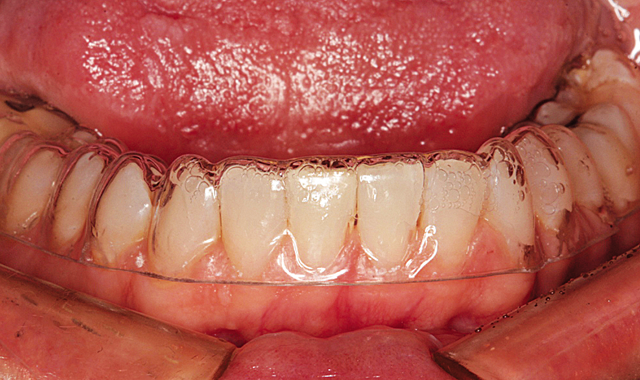

Figure 6 shows the aligners in place from the retracted facial view. The maxillary aligner at placement is shown from the incisal view in Figure 7. In Figure 8, the mandibular aligner is shown in place also from the incisal view.

Fig. 7

Fig. 8

During the next twelve weeks, Mary wore the two Inman Aligners for at least sixteen hours a day. She presented to the office for additional IPR every two weeks. The Inman Aligner can be seen in place from the incisal view on the maxillary arch after twelve weeks in Figure 9.